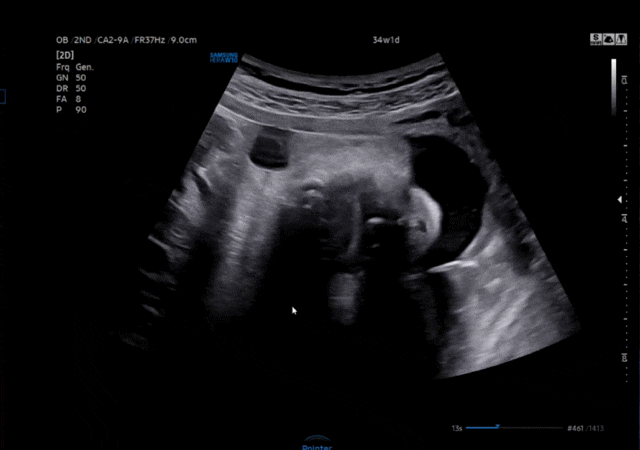

[임신 34주] 일산차병원 막달 검사 시작, 임신 후기 증상

벌써 임신 34주 진입! 임신 후기부터는 2주마다 병원 진료를 보고 있는데요, 이번엔 막달 검사도 일부 진행...